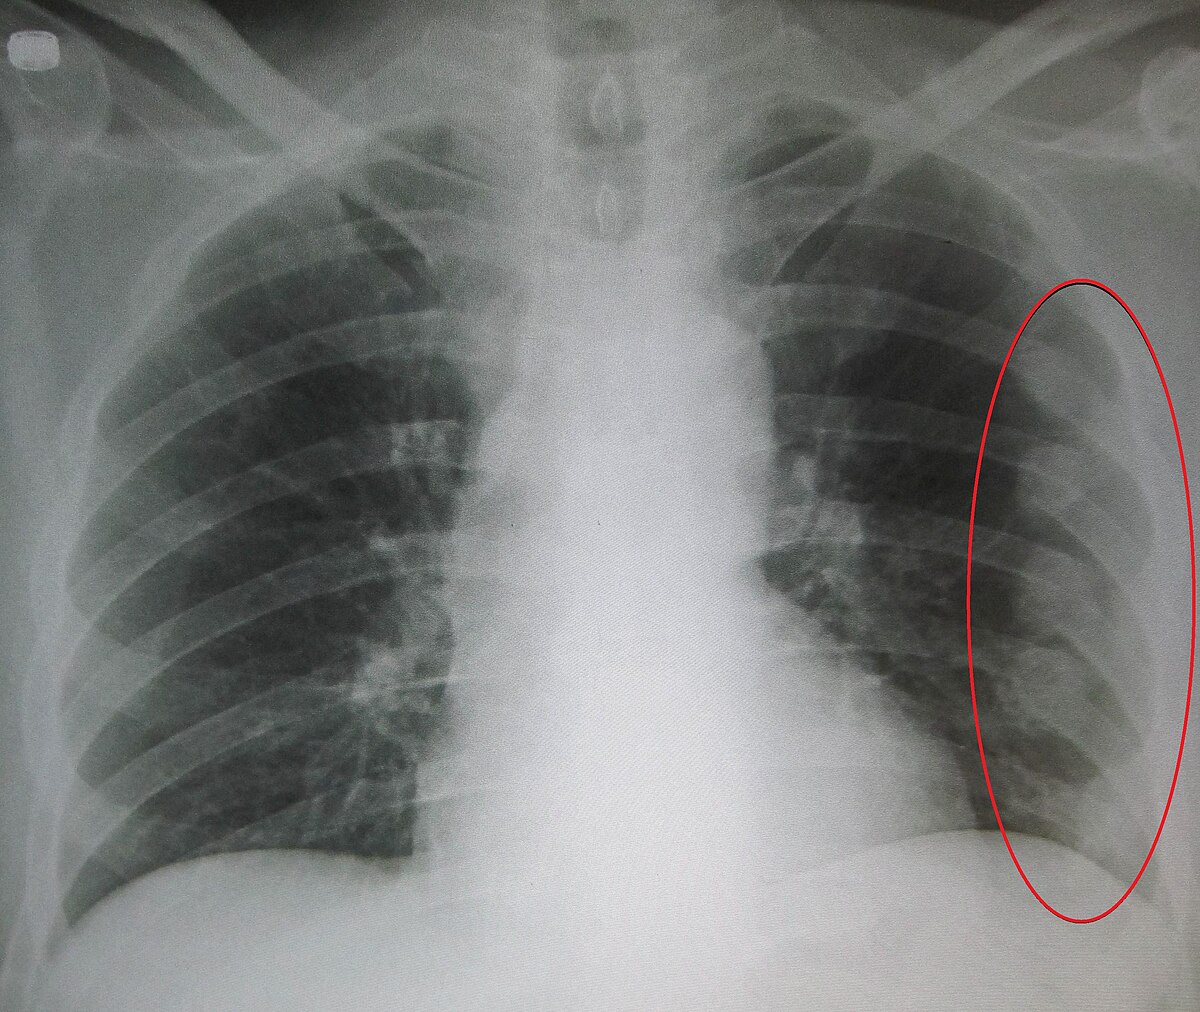

How to diagnose broken ribs. The doctor will first give you an exam to look. If you have a broken rib, symptoms such as bruising, pain and swelling are considered very Press on the injured area.

A broken rib typically causes sharp pain. To diagnose a rib injury, it’s best to see a medical professional who can look at your injuries with professional tools and technology. You may also feel or hear a crack or pop when the.

Sometimes, you may be able to feel a break in your rib by rubbing your finger over the rib. If you have a tender area on your ribs that hurts with every breath, you may have a broken rib. If you heard cracking during the injury or you hear or feel cracking when you move or.